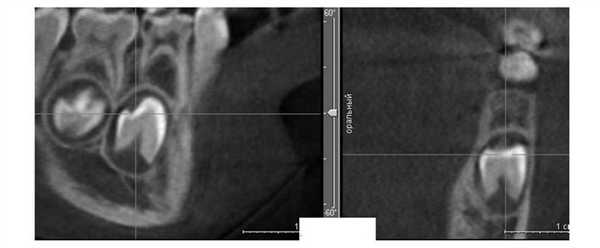

Адаптируясь к уменьшенному размеру челюстей, корни или зачатки зубов размещаются в альвеолярном отростке более компактно. Если зачатки резцов на верхней челюсти из-за недостатка пространства не могут располагаться по периметру альвеолярного отростка, они смещаются небно. При максимально компактном расположении уже постоянный центральный резец смещен небно от одноименного временного (рис. 1). Рисунок 1. Положение коронок зачатков постоянных центральных резцов за корнями одноименных временных (пациент И.Е.).

Положение корней боковых резцов за корнями центральных также отражает существенный недостаток пространства во фронтальном отделе (рис. 2), Рисунок 2. Положение корней боковых резцов за корнями центральных. а, б — пациент В.В.; в, г — пациент Х.А. при этом они равномерно располагаются в альвеолярном отростке.